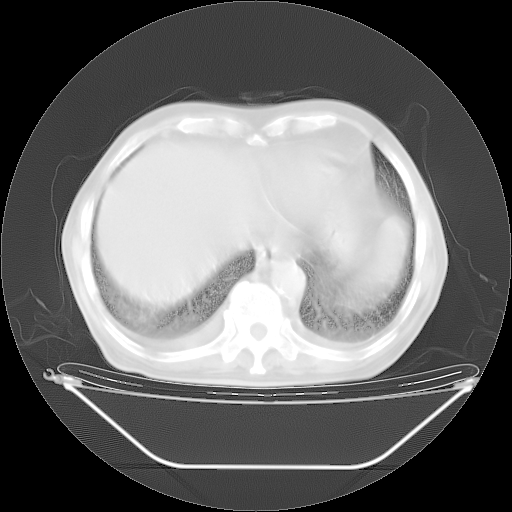

今天复查肺部CT,发现双肺广泛磨玻璃样改变。所以我把3月19日和5月9日相隔50天的肺部CT上传。请大家会诊。

2009年3月19日肺部CT片。

5月9日肺部CT(在4月27日齐鲁医院肺部CT描述部分肺组织磨玻璃样改变,12天后肺组织广泛磨玻璃样改变)